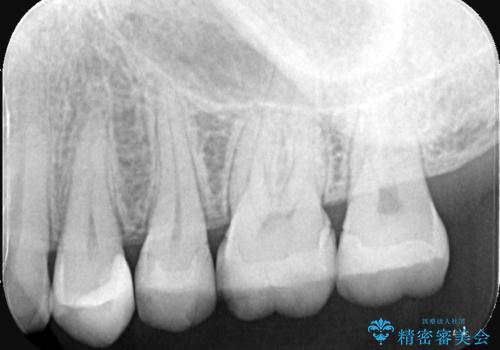

- 主訴:詰め物が欠けてしまった。

歯冠色インレーが一部欠けてしまい、他院にて部分的に樹脂のコーティング剤を付けてもらっている状態でした。

欠けている大きさが大きかったため、やり替えを提案しセラミックインレーでのやり替えとなりました。

他院にてセットしたセラミックインレーの一部が研磨では対応できない程大きく欠けてしまっていたため、やり替えとなりました。再度欠けぬよう、歯質を削り厚みを確保しています。